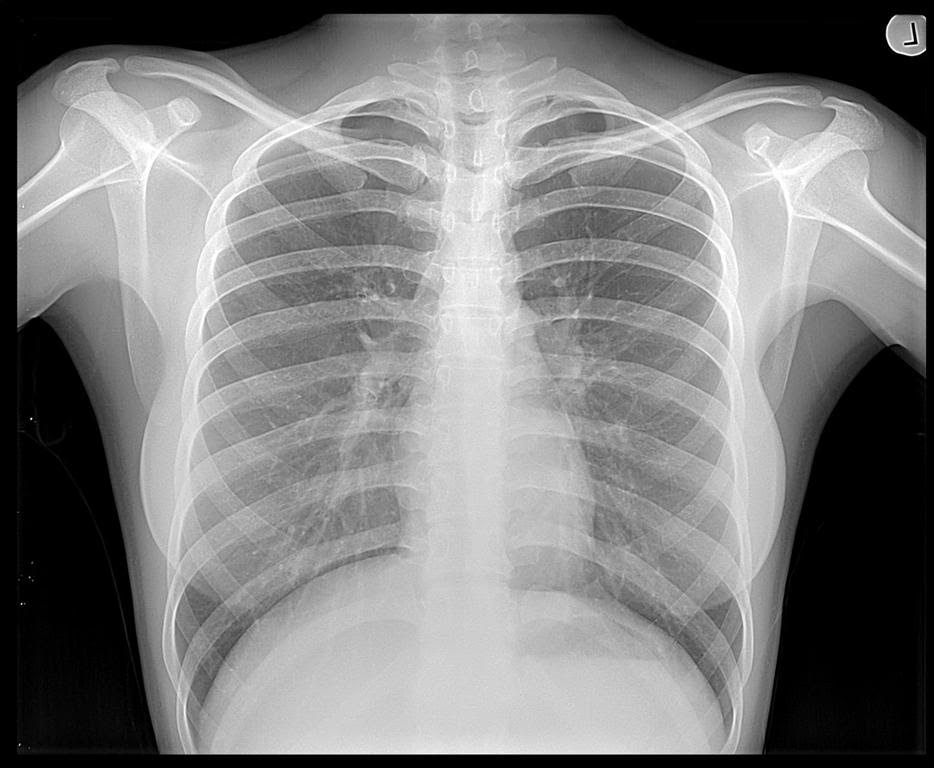

An X-ray is a quick, painless test that produces images of the structures inside your body — particularly your bones. X-ray beams can pass through your body, but they are absorbed in different amounts depending on the density of the material they pass through. Dense materials, such as bone and metal, show up as white on X-rays. The air in your lungs shows up as black. Fat and muscle appear as varying shades of gray. For some types of X-ray tests, a contrast medium — such as iodine or barium — is introduced into your body to provide greater detail on the X-ray images.

Chest

- Lung infections or conditions. Evidence of problems such as pneumonia, tuberculosis or lung cancer can show up on chest X-rays.

- Enlarged heart. One of the signs of congestive heart failure is an enlarged heart, which shows up clearly on X-rays.

- Blocked blood vessels. Injecting a contrast material that contains iodine can help highlight sections of your circulatory system so that they can be seen on X-rays.